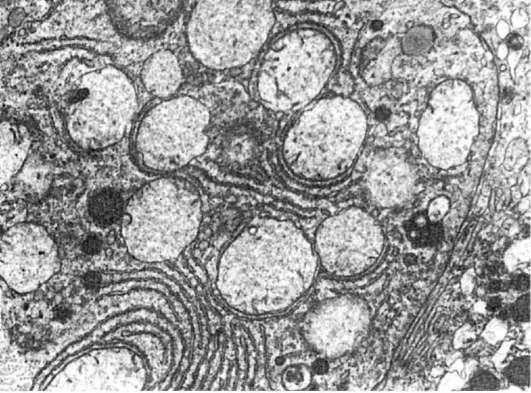

Рис.

8. Патология митоза. Полутонкий срез ткани опухоли. х1000